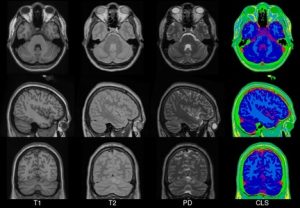

MNI152

In 2001, within the ICBM project (Mazziotta et al., 1995, 2001a,b), three sites (MNI, UCLA, UTHSCSA) each collected ~150 MRI volume images from a normative young adult population. These images were acquired at a higher resolution than the MNI305 data and exhibited improved contrast. To create MNI152 (a.k.a. ICBM152), each individual in the MNI cohort was linearly registered to MNI305. This new template exhibits better contrast and better definition of the top of the brain and the bottom of the cerebellum due to the increased coverage during acquisition. An automated analysis pipeline (Zijdenbos et al., 2002) also generated gray/white/CSF maps. The templates for image intensity (T1, T2,PD) and tissue type (GM, WM, CSF) maps have subsequently been incorporated into other popular brain mapping software, e.g. SPM, FSL AIR, LORETA,VARETA, BRAINWAVE. In 1996, regional probability maps were generated from the MNI152 database. The MRI volume from a single subject (“Jacob”) was manually segmented into 142 sub-regions. Each subject’s MRI was non-linearly registered to the Jacob atlas using ANIMAL (Collins et al., 1995, 1999), such that the atlas labels were transferred to each of the individual MRI data volumes. These labels were then linearly mapped to MNI152 space to generate regional probability maps.

Transverse, sagittal and coronal views of four generations (all T1-weighted images) of MNI space template from left to right. Note that MNI52 has greater z-axis coverage than MNI305 and that the 40th-generation non-linear MNI152 combines the detail apparent in the single subject Colin27 template with the group representativeness of MNI305 or MNI152.